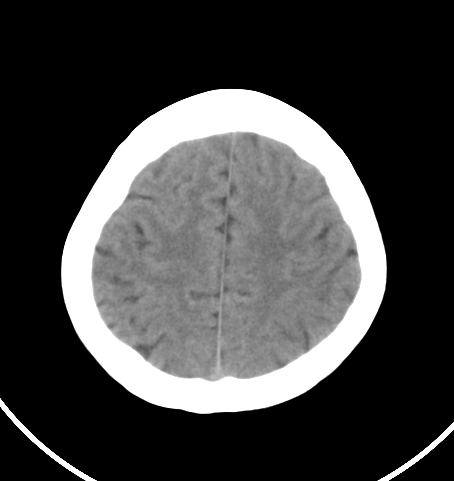

病人女 35岁 自述头晕 头痛

双侧基底节区及右侧丘脑区多发点状钙化,周围未见水肿及占位征象.余未见明显异常.考虑:脑囊虫病<囊虫的退变或死亡期>请结合有无相关病史.

未见明显异常,建议检查颈椎。